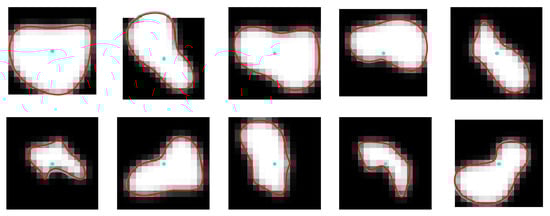

Figure 1 shows example cross-sections of a few segments in the CAT08 dataset, computed for a sampling interval of 0.45 mm. Segments s e g 01 and s e g 02 are consecutive anatomical parts of the right coronary artery (RCA). However, the sections of these segments presented in Figure 1 belong to different datasets and differ in appearance quite significantly. The contrast for the 25 images of s e g 01 is much higher and the area of its lumen region does not change as much as the lumen region for the 33 sections of s e g 02.

Thresholding would not be useful for lumen region segmentation of s e g 02. The lumen diameter noticeably decreases along the 20 sections of s e g 04 (from left to right, row by row) and approaches subpixel values in the bottom row. At the same time, bright regions in the background dominate the image content. The contrast of images in s e g 06 is good. The lumen region is well defined and its shape is close to circular. However, it shows a significant blur, similar to all other images. This property, originating in the limited spatial resolution of the CT scanners, leads to high uncertain localization of lumen boundaries, especially in noisy images.

Segments s e g 07 and s e g 08 form consecutive parts of the left anterior descending artery (LAD). The first section (the leftmost in the upper row) of s e g 07 is closest to the heart, the last section (rightmost in the lower row) is the immediate neighbor of the first section in s e g 08. The sections in the upmost row of s e g 08 exhibit a reduced lumen area and bright image spots in the sixth and seventh sections, apparently caused by atherosclerotic plaque. If they become part of the lumen model as a result of image analysis, postprocessing will be needed to detect and quantify them. s e g 12 is the first obtuse marginal artery (OM1). Its lumen is well distinguished from the immediate background. However, a significant area is occupied by black triangular-shaped regions where the normalized intensity is close to zero (−300 HU or less in the scanner-acquired CT volumes). The typical cross-section shape of the vessel lumen marked by the observers is neither circular nor elliptical (Figure 4).